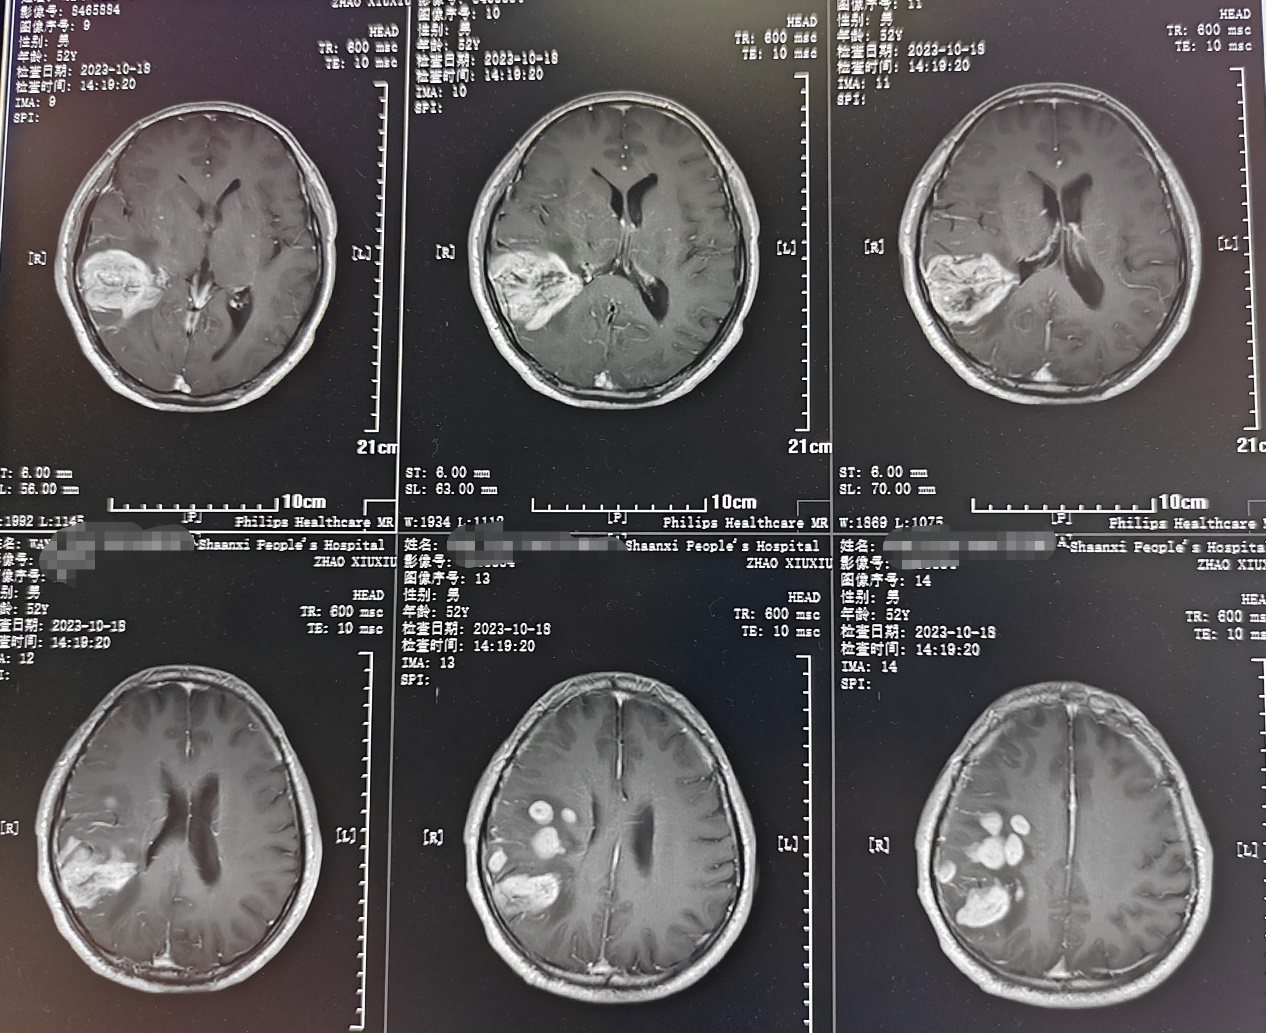

患者为成年男性,因头痛伴间断晕厥1月,在当地医院检查发现右颞顶叶多发占位病变,考虑胶质瘤。因肿瘤功能区关系密切,术后可能出现肢体运动障碍。如何做到在尽量全切肿瘤同时做好神经功能保护,对于神经外科医生来说是一种挑战。术前全科详细讨论病例制定了手术方案,决定在电生理监测下进行手术,近日由缪星宇主任医师、孟发财副主任医师、刘凯飞主治医师成功为患者实施了手术。术中在电生理运动诱发电位的监测下,结合多模态影像技术,显微镜下全切肿瘤,成功利用电生理监测技术保留运动区结构和功能,术后患者恢复顺利,病理结果确定胶质瘤诊断。

神经电生理监测是神经外科手术中监测神经功能完整性、减少神经损伤、提高手术质量所必不可少的组成部分,也是神经外科手术功能区保护的金标准。该患者采用的术中运动诱发电位监测是神经电生理监测技术之一,通过经电刺激神经或皮层,对照操作前的肌肉复合动作电位波幅和潜伏期基线,可判断神经、传导束的功能变化情况,为手术中实时监测神经功能提供有用的信息,是神经外科手术中常有监测技术之一,广泛用于颅脑和脊髓手术。在诱发电位的监测下,可以早期判断神经的位置和走形,监测神经功能变化,避免神经损伤。